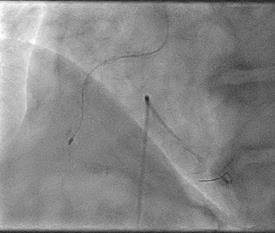

Can thiệp ngã ba động mạch liên thất trước và nhánh chéo 1 với hai stent có bọc thuốc bằng kĩ thuật cullote. Tiếp tục can thiệp động mạch vành phải với ống thông can thiệp (guiding catheter) (Cordis JR4 cm 6Fr) và dây dẫn (Asahi Sion 0.014”). Nong tổn thương bằng bóng 3.5 x 15mm (Neich Sapphire), bóng 4.0 x 12 (NC Quantum Apex), bóng cắt 3.5 x 15 (Cutting balloon, Angiosculpt) không làm vỡ được mảng vữa xơ. Quyết định dùng hệ thống khoan cắt mảng vữa xơ với dây dẫn mềm (Boston Scientific Rotablator Rotalink Plus) và mũi khoan (burr) 1.5mm. Tuy nhiên vì kích thước động mạch quá lớn nên mũi khoan đi qua tổn thương mà không chạm vào mảng vữa xơ được. Chuyển sang mũi khoan có đường kính lớn hơn 2.15mm với tốc độ khoan 150000 vòng /phút. Khi mũi khoa đi qua được 1/3 tổn thương thì không thể di chuyển được tiếp. Nhận định tại thời điểm đó là mũi khoan bị kẹt trong tổn thương tại đoạn giữa của động mạch vành phải. Ngay lập tức các bác sỹ có kinh  nghiệm can thiệp trong bệnh viện được mời đến phòng can thiệp đồng thời thông báo cho các phẫu thuật viên tim mạch chuẩn bị trong trường hợp cần thiết. Bệnh nhân có biểu hiện đau tức ngực trái, tuy nhiên mạch và huyết áp tương đối ổn định, điện tim không thay đổi. Dòng chảy trong động mạch vành còn duy trì nhưng chậm TIMI 2. Sau khi hội ý, hướng xử trí đầu tiên là dùng dây dẫn cứng Conquest Pro (Asahi) để đi qua tổn thương nhưng không thành công. Sau đó chúng tôi quyết định cắt đoạn đầu của hệ thống nối mũi khoan, đưa ống thông heartrail (Terumo) sát vào mũi khoan nhằm thay đổi tư thế và cố định mũi khoan vào dây dẫn để đưa ra ngoài. Cuối cùng mũi khoan được đưa ra ngoài thành công. Tổn thương tiếp tục được nong bằng bóng cắt và bóng áp lực cao và đặt được giá đỡ kim loại (stent) bọc thuốc 4.0 x 26mm. Kết quả là động mạch vành được mở rộng hoàn toàn, bệnh nhân không còn đau ngực, huyết động ổn định.

Hình 1: A- hình ảnh động mạch vành trước can thiệp; B - dùng bóng cắt (cutting balloon) không phá vỡ được cấu trúc mảng vữa xơ; C – mũi khoan 1.5 không chạm vào được mảng vữa xơ vôi hóa; D – mũi khoan 2.15 bị tắc tại vị trí hẹp.